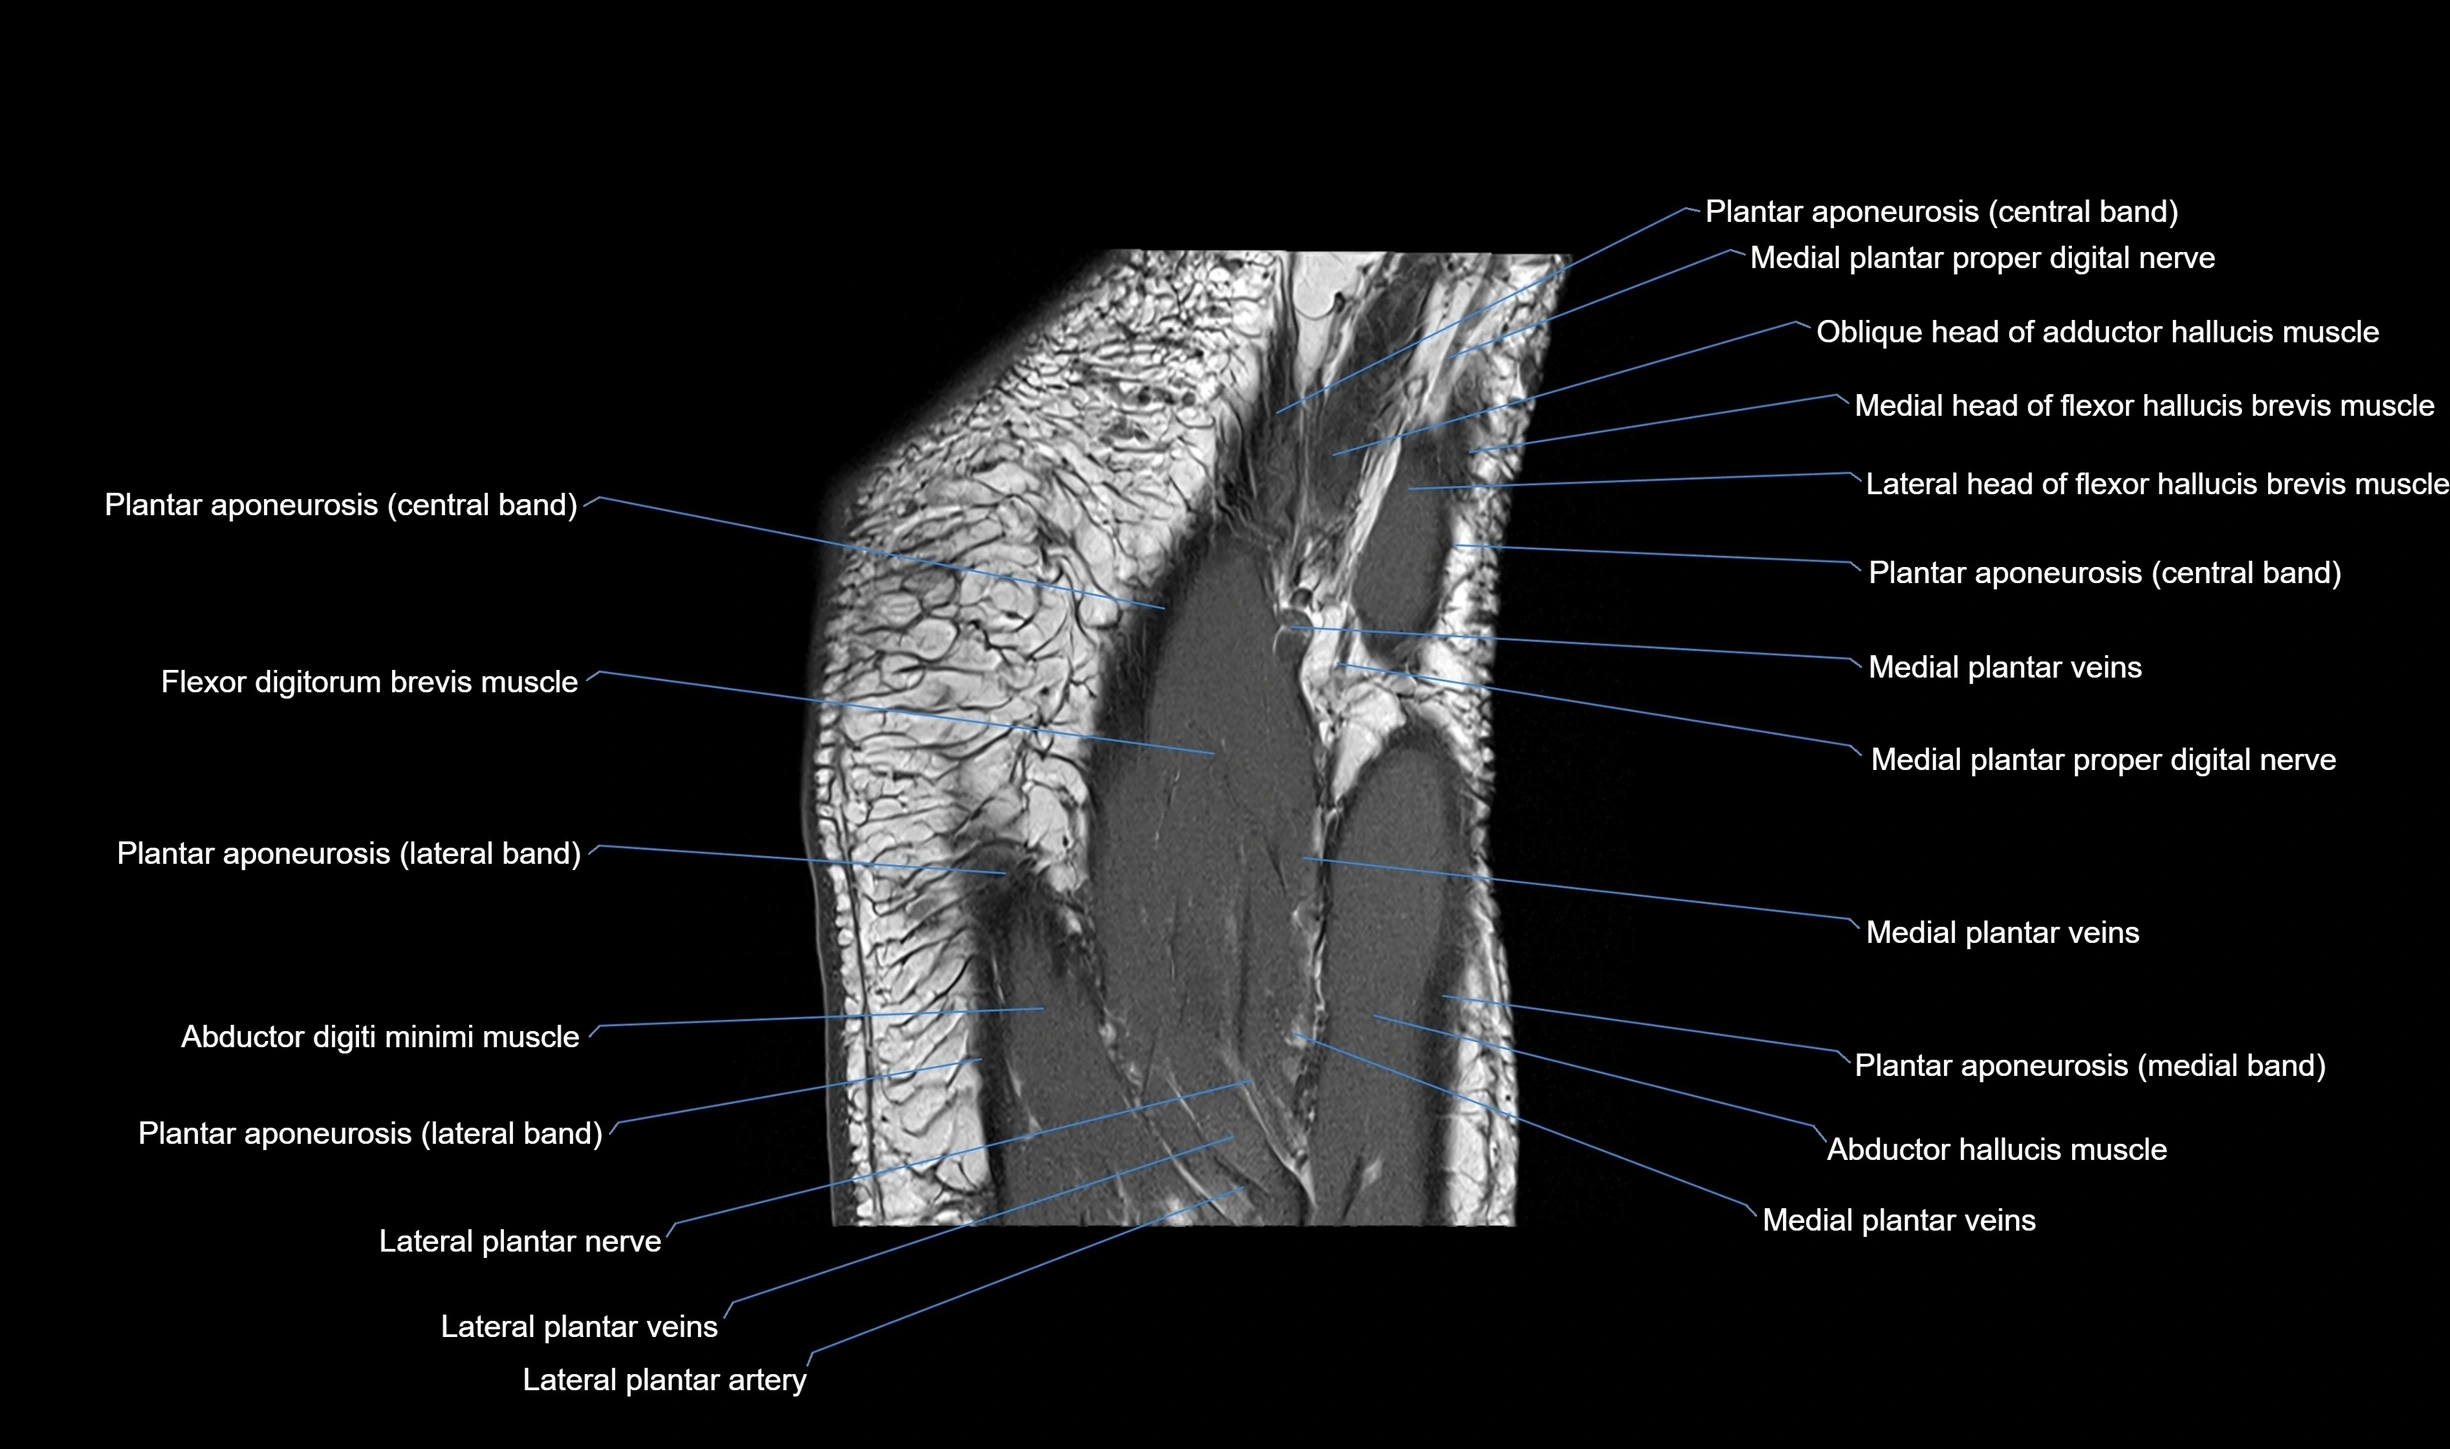

MRI image